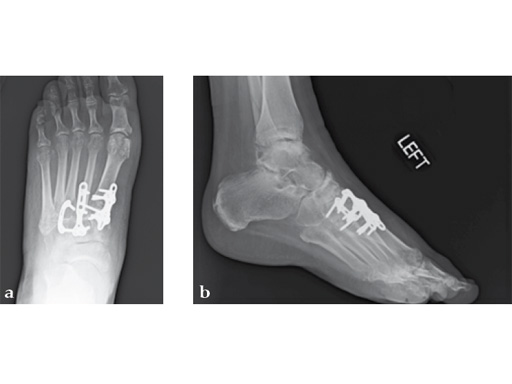

Case 8: VA -locking X-plate

The patient was treated with arthrodesis of the talonavicular and subtalar joints. The compression/ distraction device was used to restore the length of the medial column. The articular surface of the subtalar joint was prepared arthroscopically. The talonavicular joint was debrided then packed with a tricalcium matrix. Length was maintained using a locking X-plate. The subtalar joint was then fixed with a 6.5 mm headless compression screw.

The patient returned to work 3 months after surgery. He wears an ankle brace when on uneven surfaces. His lateral column and subtalar pain have resolved.